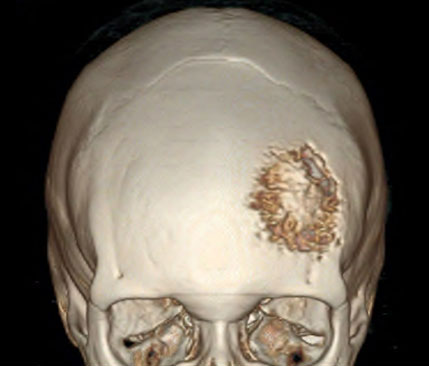

如果是比较恶性的脑膜瘤,已经侵犯了颅骨,这个时候我们就要把被侵犯的颅骨切除,然后再用人工的钛金属网修补颅骨。

这是利用钛合金制作而成的人工颅骨修补材料,轻便,结实,而且可以做磁共振。